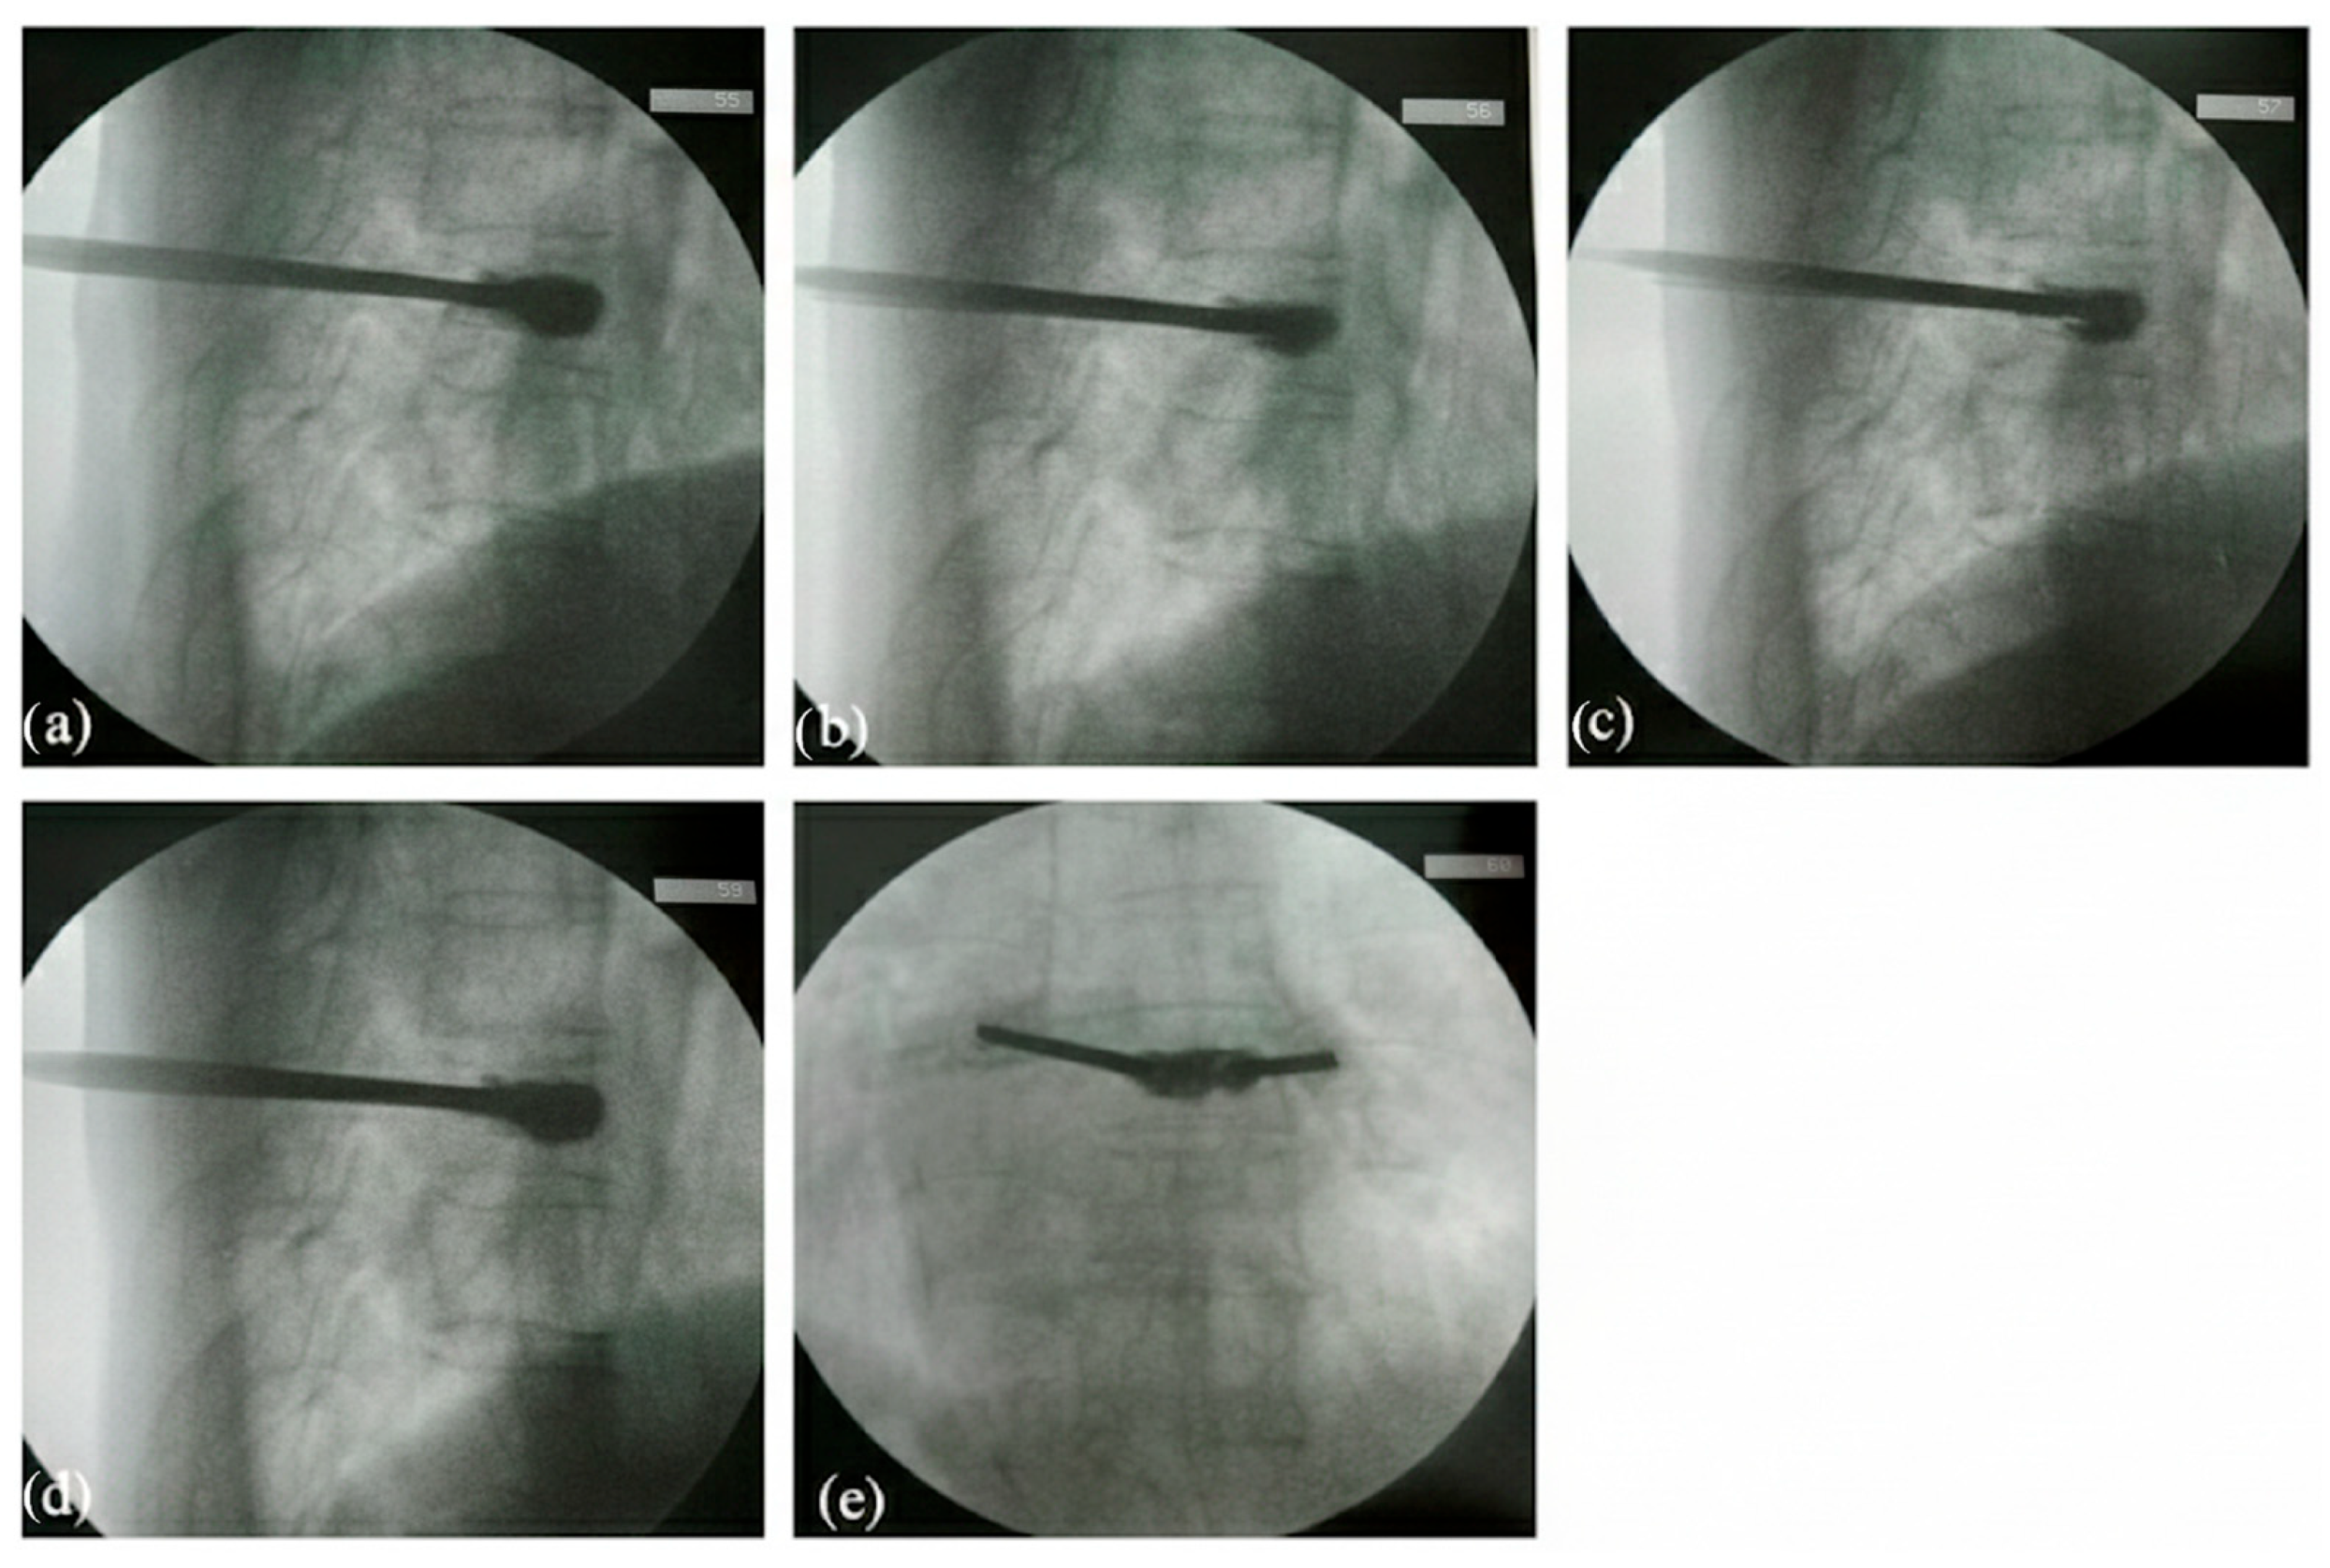

3.1. Surveillance of Cement Leakage

3.2. Decompression Maneuver

3.3. Postoperative Clinical and Radiographic Outcomes